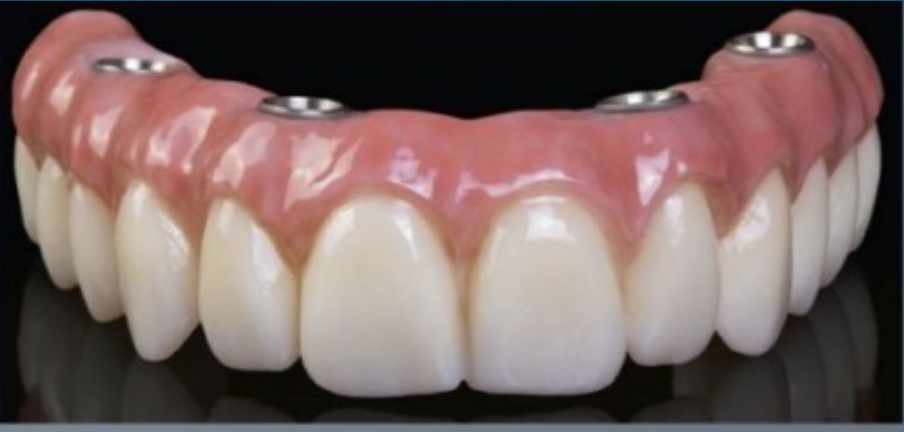

(38.) Convex intaglio surface.

Figure 38

(39.) Convex intaglio surface.

Figure 39

(40.) Convex intaglio surface.

Figure 40

(41.) Convex intaglio surface.

Figure 41

Intaglio Profiles in Edentulous Areas

The profiles of the intaglio surfaces facing edentulous areas should be convex like modified ridgelap and ovoid pontics, so these surfaces are accessible and cleanable (Figure 38 through Figure 41).